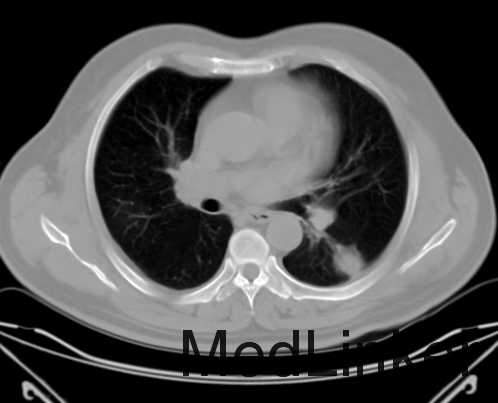

查体: 体温:36.3℃ 脉搏:78次/分 呼吸:20次/分 血压:130/82mmHg。双眼睑紫红色水肿斑,颜面部、颈部、前胸上部弥漫性红色皮疹,不凸出于皮面,伴瘙痒、无破溃、压痛,全身浅表淋巴结未触及肿大。唇红,咽无充血,扁桃体不大。气管居中,甲状腺未触及肿大。双肺呼吸音粗,双肺底可闻及少许啰音,心率78次/分,律齐,各瓣膜听诊区未闻及病理性杂音,腹软,全腹无压痛、反跳痛,肝、脾肋下未触及。脊柱呈正常生理弯曲,活动度好,无压痛,四肢无畸形,双侧“4”字试验阴性,肌力及肌张力正常,关节无红肿,运动正常,双下肢无水肿。生理反射存在,病理反射未引出。 辅助检查 免疫功能:总T淋巴细胞476个/ul,总B淋巴细胞55个/ul,Th细胞392个/ul,Ts细胞69个/ul,Th/Ts5.66 ,NK细胞36个/ul,T淋巴细胞+B淋巴细胞+NK细胞589个/ul。 骶髂CT示:双侧骶髂关节退行性变。 骨密度示:(左前臂)骨质疏松,(腰椎+左髋)骨量正常。 肌电图:肌源性损害,不排除多发性周围神经损害。 血常规:白细胞数 7.21 ×10^9/L,红细胞数 4.22 ×10^12/L,血红蛋白浓度 129.0 g/L,血小板数 180.00 ×10^9/L,淋巴细胞绝对值 1.02 ×10^9/L。 血沉 24.00 mm/h。 术前免疫:乙肝表面抗体 阳性(+) >1000 IU/L,乙肝e抗体 阳性(+) 0.045 COI,核心抗体 阳性(+) 0.007 COI,乙型肝炎病毒DNA <1.0*10^2 IU/mL,余(-)。 生化系列:低密度脂蛋白 2.46 mmol/L,高密度脂蛋白 1.01 mmol/L,甘油三酯 1.79 mmol/L,总胆固醇 3.95 mmol/L;羟丁酸脱氢酶 234.00 U/L,乳酸脱氢酶 301.00 U/L,肌酸激酶同工酶MB 9.50 U/L,肌酸激酶 18.00 U/L;白蛋白 33.50 g/L。 心肺四项大致正常。降钙素原 0.09 ng/ml。 特种蛋白:免疫球蛋白G 9.87 g/L,免疫球蛋白A 1.87 g/L,免疫球蛋白M 2.77 g/L,补体C3 0.74 g/L,补体C4 0.15 g/L,C-反应蛋白 3.34 mg/L。 免疫功能:总T淋巴细胞 993 个/ul,总B淋巴细胞 195 个/ul,Th细胞 676 个/ul,Ts细胞 291 个/ul,Th/Ts 2.32,NK细胞 42 个/ul,T淋巴细胞+B淋巴细胞+NK细胞 1270 个/ul。T-SPOT(-)。 胸部正位片可见纹理增粗。 胸部CT示:右肺上叶、双肺下叶炎症,左肺下叶结节,双侧胸膜增厚。